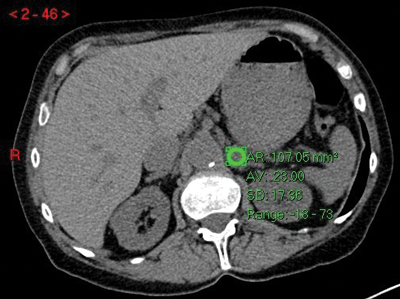

where E is the HU on the early post-IV contrast scan, D is the delayed scan and U is the unenhanced scan. A cut-off of >60% has been shown to diagnose a benign adenoma with a sensitivity of 88% and a specificity of 96% [5] (Figure 3).

Figure 3:

Top: Unenhanced CT (HU 23).

Centre: Arterial phase CT (HU 74).

Bottom: Delayed phase CT (HU 37).

Absolute washout = (74-37)/(74-23)x100 = 37/51x100 = 72.5% in keeping with adenoma.